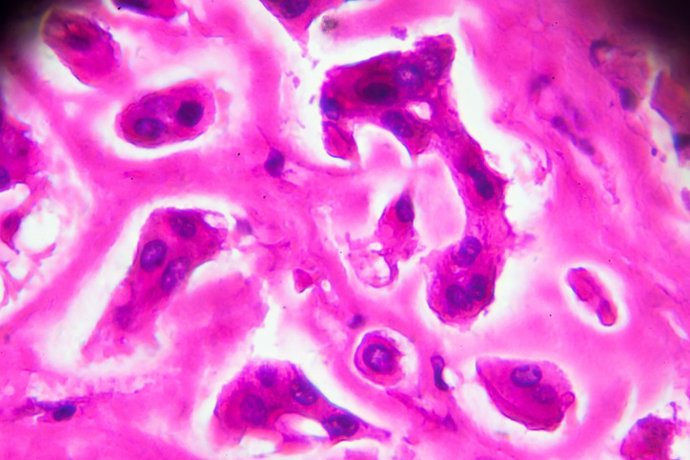

Archivo - Muestra patológica cutis de la lepra de los lepromatosa bajo microscopia ligera

Archivo - Muestra patológica cutis de la lepra de los lepromatosa bajo microscopia ligera - JXFZSY/ ISTOCK - Archivo